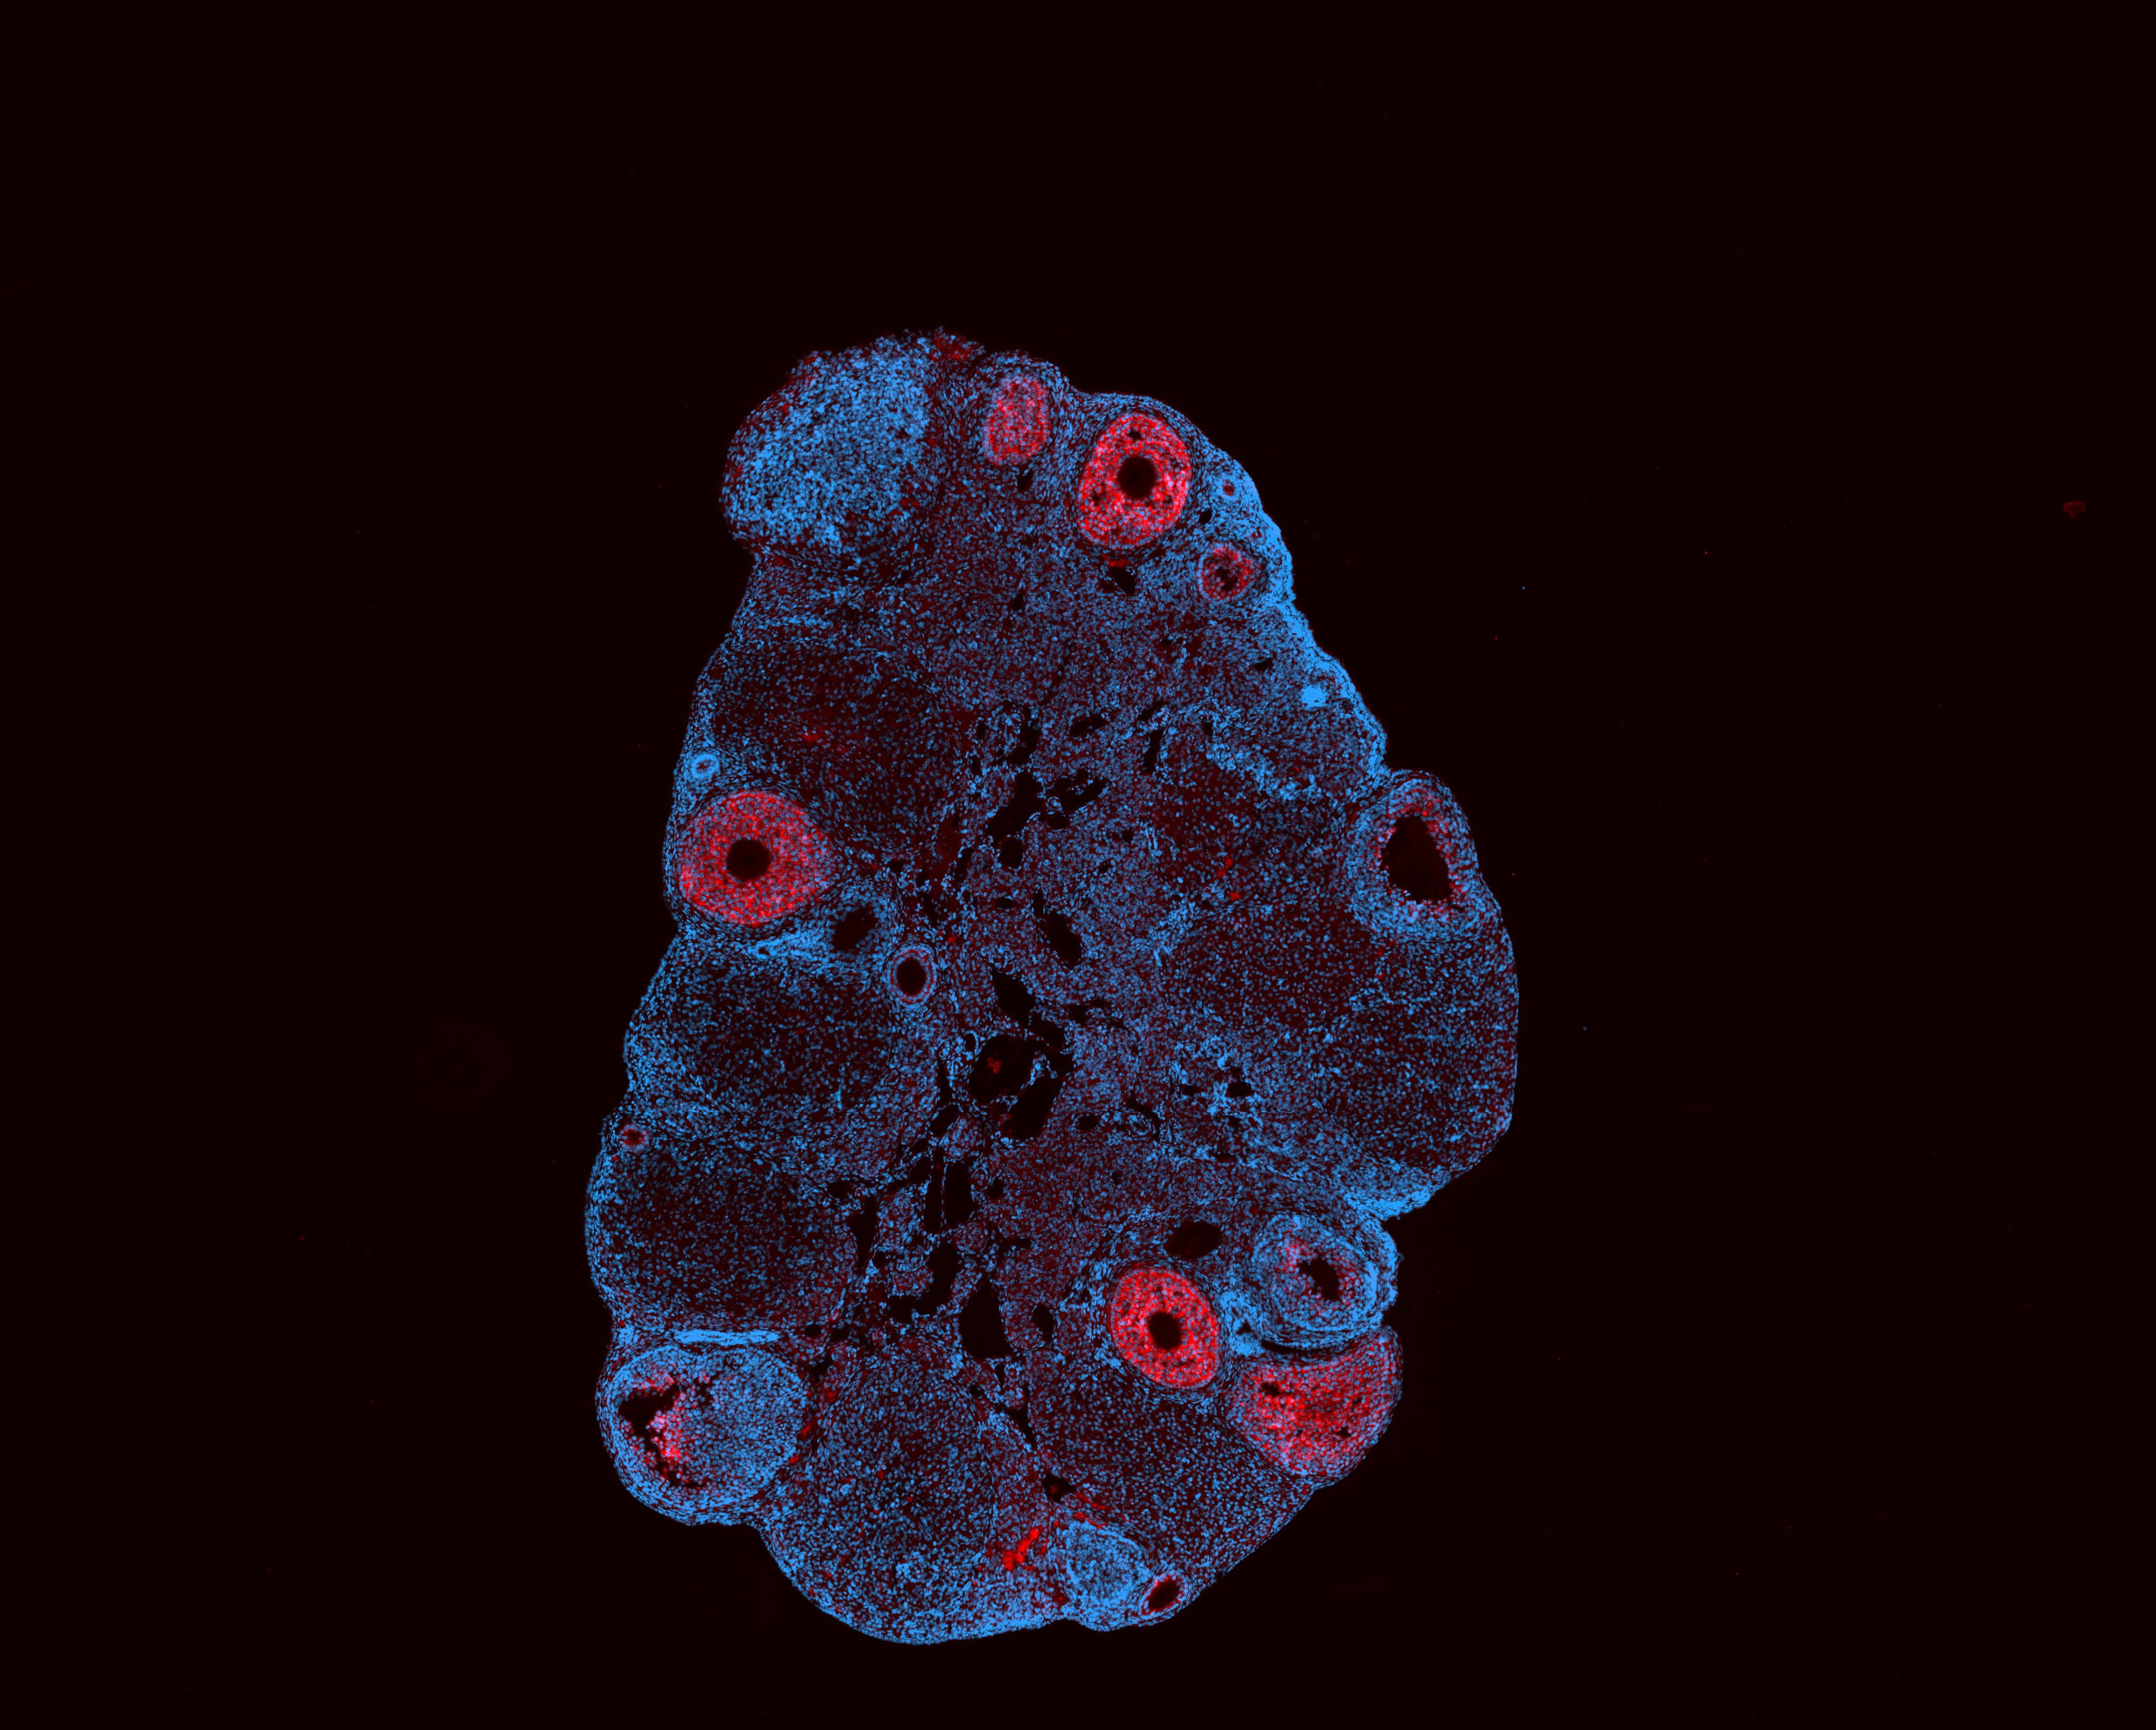

What scientists know so far is that women’s ovaries begin aging earlier, and at a much faster rate, than the rest of their bodies. This is different from male reproductive aging, which begins in the 40s and continues gradually until death, usually without serious symptoms, Huang explained.

Huang’s team, a group of around 20 researchers from across the world, uses a mixture of lab-based research, human trials and population modeling to identify the biomarkers of reproductive aging by observing changes in blood and tissues.

One of ACRLE's main goals is determining the link between the ovaries and women’s overall health, which Huang believes is strong. “There’s enough good epidemiological data to show that women who are able to conceive later in life are able to live longer,” he said.

Women who experience menopause prematurely, in their 30s and early 40s, are at increased risk of cardiovascular problems, osteoporosis and metabolic disease for the remainder of their lives, implying the biological impact of menopause continues far beyond a woman’s final period, Huang added.

Huang hopes his research will help doctors diagnose, treat and potentially delay menopause in the future. “Knowing that menopause is a part of aging but that we can do something about it and there are solutions out there … brings a lot more autonomy to women,” he said.

Some scientists think East Asia could hold the key to a natural HRT alternative. “Something that is specific and unique within the region is traditional Chinese medicine,” Huang said. “Exciting” preclinical research from China shows that some herbal remedies have an impact on ovarian aging, he added.